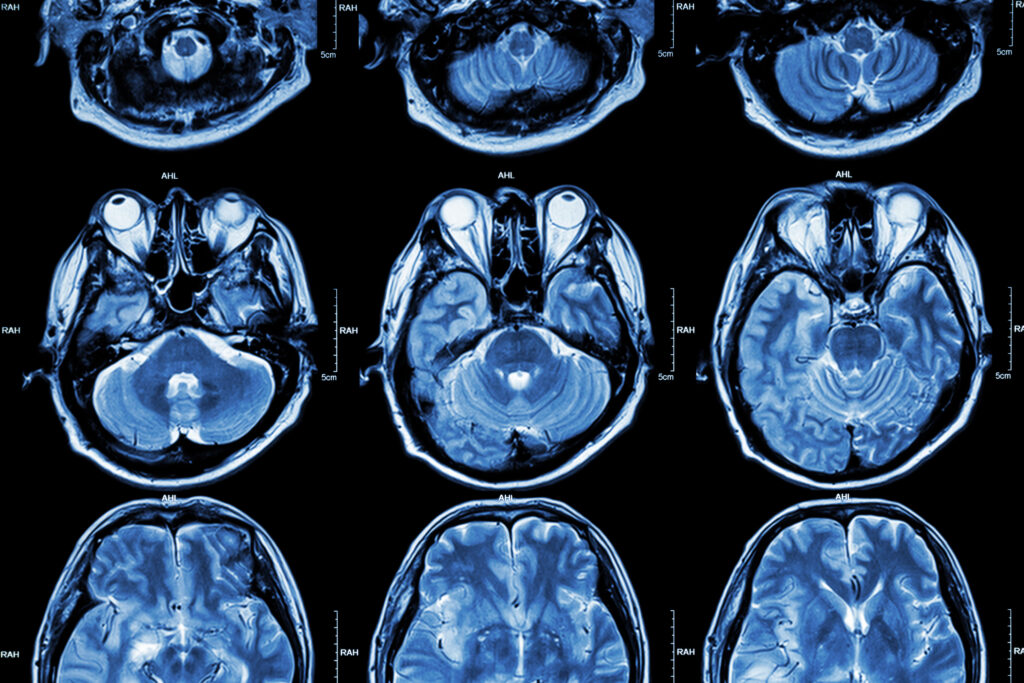

Pour mener leurs travaux, les scientifiques ont étudié le cerveau de 25 chats de différents âges, dont plusieurs montraient des signes de troubles cognitifs avant leur décès. Leur analyse à révéler une accumulation de bêta-amyloïde, cette protéine toxique qui s’agglutine entre les neurones et perturbe leur communication, un marqueur bien connu de la maladie d’Alzheimer chez l’homme.

Ils ont aussi identifié la présence de dépôts dans les synapses, ces jonctions qui permettent la circulation de messages entre les cellules neuronales. Avec l’âge, le mécanisme de “nettoyage” naturel des synapses endommagées par des cellules de soutien devient trop agressif. Résultat : une perte accélérée de connexions, entraînant des troubles de la mémoire et des capacités cognitives.